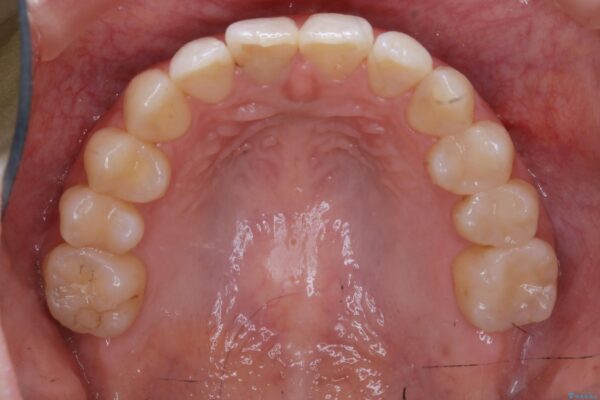

治療前

20代 女性 非抜歯で歯列をコンパクトに20代 女性 非抜歯で歯列をコンパクトに20代 女性 非抜歯で歯列をコンパクトに